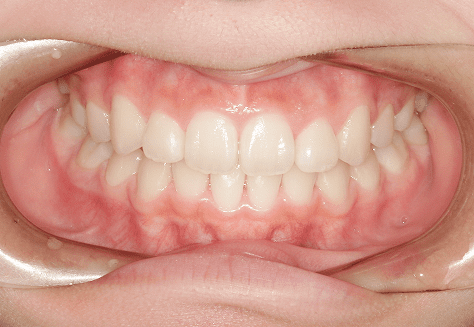

M.M

治療前

治療後

主訴

嚙み合わせが悪い。八重歯が気になる。

診断

叢生・反対咬合

年齢/性別

10代/女性

抜歯部位

非抜歯

使用装置

インビザラインファースト→インビザラインフェーズⅡ(部分的にワイヤーにて処置)

保定装置

上下ビベラリテーナー

基本料金

円ファースト時:450,000円

フェーズⅡ時:240,000円 -

診察料金

ファースト時:0円×16回

フェーズⅡ時:5,500円×9回

ワイヤー併用時:8,800円×2回 -

治療期間

2年7カ月